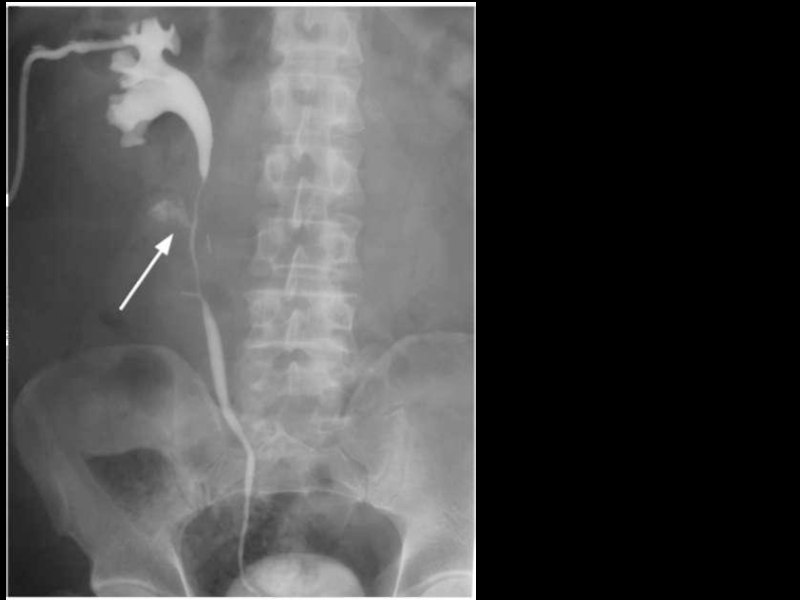

Слайд 12Разрыв левой почки

Разрыв левой почки